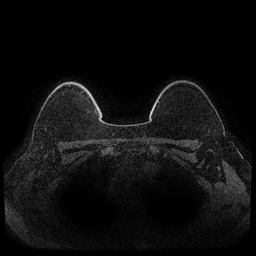

MRI images. The data used in this study are from the DUKE Breast Cancer Dataset [23], a comprehensive single-institutional retrospective collection of 3D MRI scans from over 900 patients with biopsy-confirmed invasive breast cancer at a university hospital. Each study includes a 3D MRI acquired using 1.5T or 3T scanners, from patients in the prone position. On average, each 3D scan consist of 250 2D slices (see Figure 1). For the predictive tasks, the slices are categorized into two groups: those containing breast tumors and those without. Following the approach of [15, 12], we establish a buffer zone between slices containing tumors and those that do not (highlighted in yellow in Figure 1(a)). Images within this buffer zone are excluded from analysis, and the remaining slices are labeled and used for the predictive task.

Magnetic field strength. 3T scanners offer higher magnetic field strength, improving signal-to-noise ratio (SNR) and image resolution for sharper, more detailed images [24]. However, they are more prone to artifacts, heating effects, and signal loss, especially around metal implants [5]. As such, our proposed dataset involving this spurious signal features a non-local spurious signal that influences the entire image rather than a localized region. An example set of images obtained from 1.5T and 3T devices are provided in Figure 3, showing that it is visually not possible to distinguish 1.5T MRIs from the 3T ones.